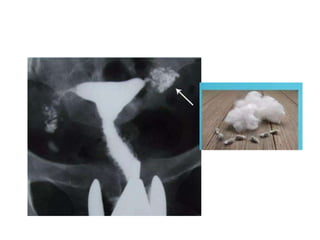

-cotton wool appearance

• HSG Findingsin genital tube -lead pipe appearance -beaded appearance -tobacco pouch appearance -golf stick appearance -cotton wool appearance -cobble stone appearance

• #31 Distribution of contrast in reticular pattern producing cotton wool plug appearence